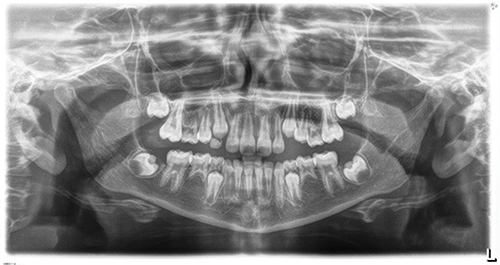

One orthodontist stepped in to clarify that the 7s appeared present, with likely absence of 8s, and pointed out that at only 9 years old, tooth development could still surprise them. “This is the kind of case where you extract the Es, take a panoramic in two years, and suddenly some of the 5s have started to form” (Fig. 5).

Fig. 5